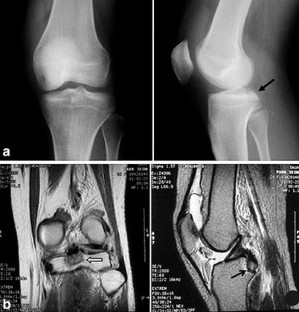

This study reports a case of unusual vascular complication related to the staple fixation for the tibial avulsion fracture of the posterior cruciate ligament (PCL). The patient, who experienced recurrent hemarthrosis 12 months after staple fixation for the avulsion fracture of the PCL, was successfully managed by removing the staple and suturing the bleeding focus of the popliteal artery. Injury to the popliteal artery by the prominent staples could be the culprit causing the recurrent hemarthrosis. This type of delayed popliteal artery injury should be kept in mind in open reduction and internal fixation for the tibial avulsion fracture of the PCL.

Fig. 2